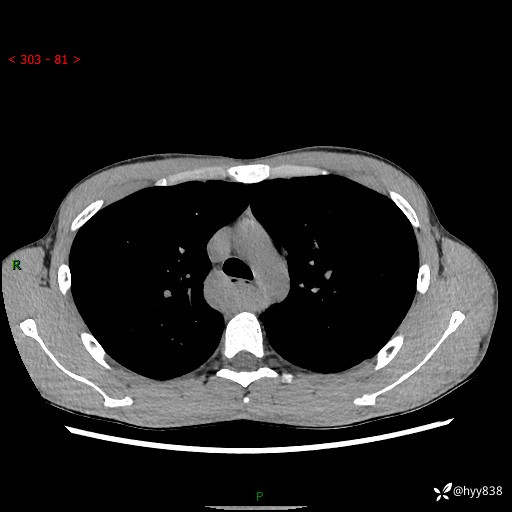

年轻男性,发现后纵隔占位1周余。征象简单,难在定位---结果公布~

现病史:患者于1周前体检行检查发现后纵隔占位,患者平素无明显咳嗽咳痰,无心慌、胸闷、胸痛、呼吸困难、低热、盗汗,无头痛、头晕,无腹痛、腹胀等不适。现患者欲求进一步治疗,遂来我院就诊,以“纵隔占位”收入我科。 患者自起病以来,精神可,睡眠可,饮食可,大小便正常,体重无明显改变。

胸部CT平扫+增强